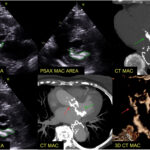

A miocardiopatia hipertrófica (MCPH) é a cardiomiopatia hereditária mais comum, com diferentes genótipos e fenótipos amplamente conhecidos. A MCPH apical, por sua vez, é notadamente conhecida por ser um subtipo bastante desafiador, seja quando falamos no diagnóstico ou no manejo desses pacientes.

O objetivo da publicação era (1) caracterizar o padrão de SGL e os índices de trabalho miocárdico nos pacientes com MCPH apical comparando com pacientes com MCPH não apical e (2) descrever a associação entre os índices de trabalho miocárdico com variáveis clínicas, bem como (3) com os achados de ressonância magnética, particularmente a presença de realce tardio, um marcador de fibrose miocárdica.

Uma análise retrospectiva de 48 pacientes com MCPH apical e 69 pacientes com MCPH não apical com medidas do SGL, índice de trabalho global (GWI), trabalho construtivo global (GCW), trabalho global desconstrutivo (GWW) e índice global de eficiência (GWE). Essas informações foram, posteriormente, comparadas com dados de ressonância magnética (RM) cardíaca de 34 pacientes com MCPH apical e de 51 pacientes com MCPH não apical.